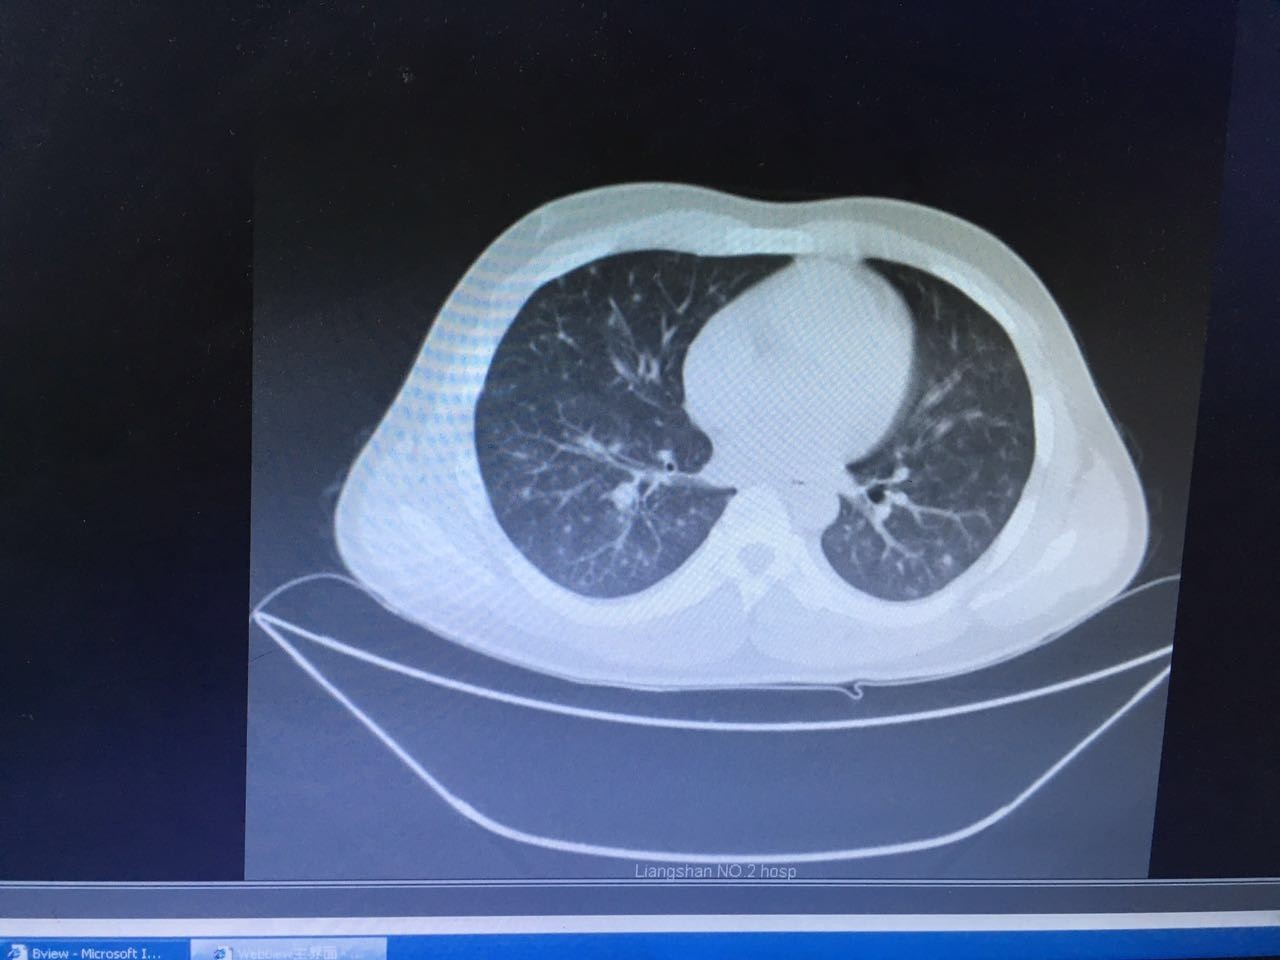

第二天,肺部CT做下来,我们傻了,和胸片差别太大了!从中下肺开始,那是大片的阴影啊!CT提示为间质性肺炎,找放射科主任读片,认为不符合肺结核、肺癌的表现(图1-3.)马上再回到病床前再次确认——没有吸烟史、没有慢性咳嗽史、没有咯血、没有盗汗史。再查体:浅表淋巴结确实不肿大,双肺呼吸音可以算略粗糙也可以算清晰。——这么这么静默的肺部体征,这么这么差的影像学结果,马上补查肿瘤标志物和自身免疫全套吧!

图1

图2

图3